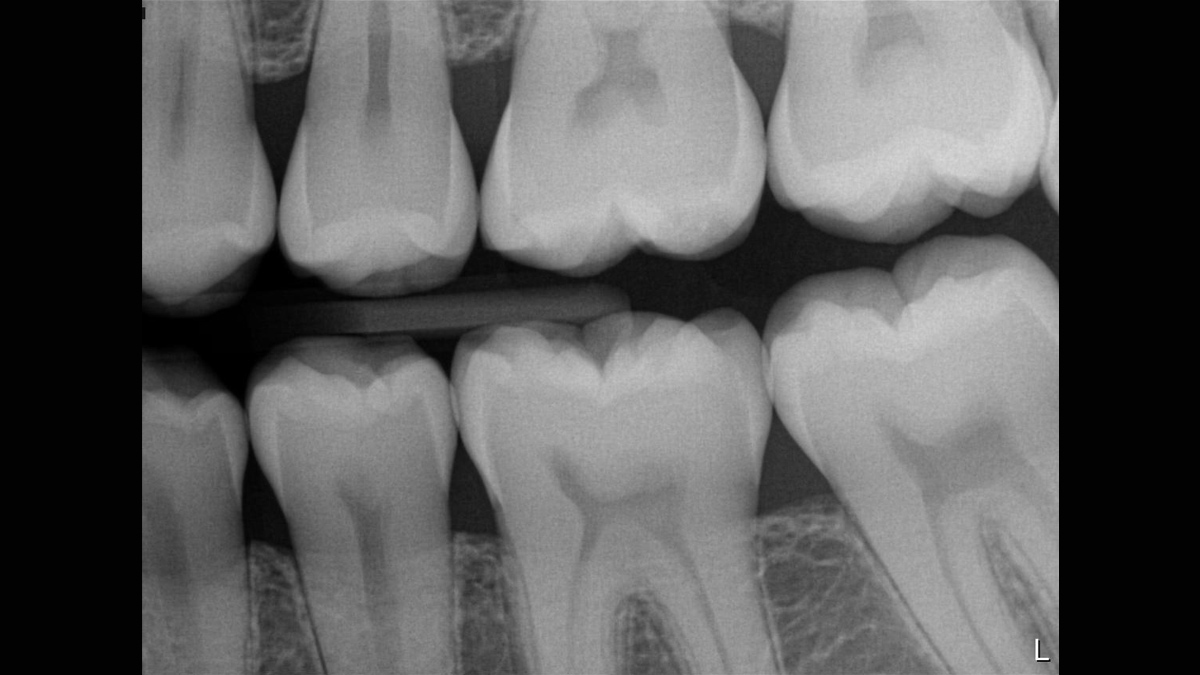

Excellent Image Quality

Schick 33 provides a theoretical resolution of 33 lp/mm and a 15 μm pixel size delivering superb image quality without the additional wait time caused by a developing or scanning process.

Schick 33 - Gallery of Sample Images